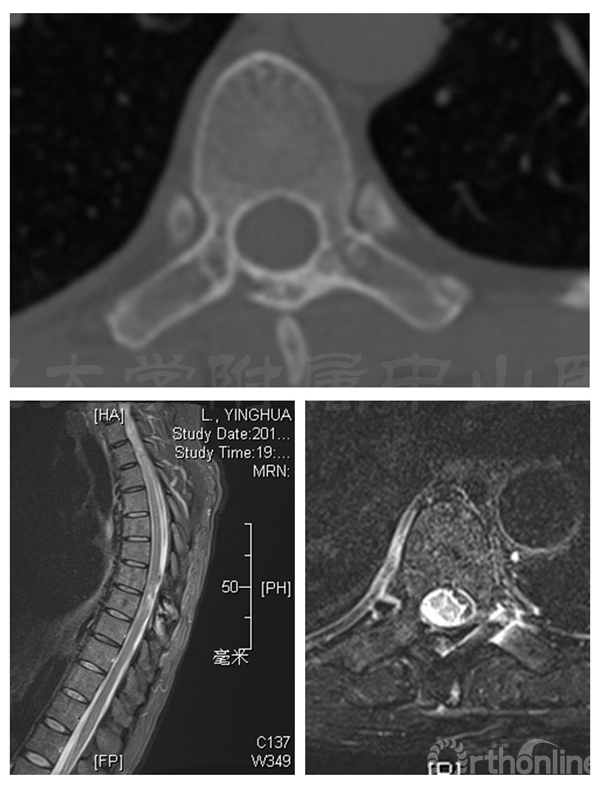

术前MRI:T7-8水平椎管内占位伴脊髓变性,脊膜瘤可能的大

术后三个月患者腰背痛完全缓解,肌力已恢复至5级,下肢麻木感消失。CT显示:椎板截骨面已骨性愈合,无移位,椎管容积与术前无明显差异

术后半年CT显示两侧椎板截骨面均已骨性愈合,椎管体积无减少。MRI显示椎管内脊膜瘤无复发